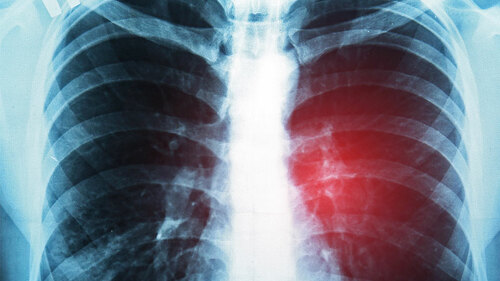

Eine fett- und kohlehydratreiche Kost begünstigt, vor allem in Verbindung mit Bewegungsmangel, Alkohol- und Nikotingenuss, Ablagerungen in den arteriellen Blutgefäßen. Wenn diese Plaques die Herz- oder die das Gehirn versorgenden Arterien sukzessive verschließen, dann droht ein Herzinfarkt oder ein Schlaganfall und eine Bypass-Operation ist in diesen Fällen oftmals die letzte medizinische Alternative, um den Blutfluss in den Arterien wieder zu verbessern und einen Infarkt abzuwenden.

Sofern ein Gefäßverschluss nicht rechtzeitig erkannt wird, ist ein Herzinfarkt oftmals die Folge einer unzureichenden Durchblutung des Herzmuskels. Ein stechender Schmerz in der Brust, Schweißausbrüche und Panikattacken sind die klinischen Anzeichen und nur ein schneller Transport des Patienten in ein Krankenhaus sichert eine Schadensbegrenzung und dem Patienten oftmals auch das Überleben. Auch in Zeiten modernster medizinischer Versorgung steht der Herzinfarkt bei Männern auf Platz 3 und bei Frauen auf Platz 4 der häufigsten Todesursachen.

Für die Diagnose eines Herzinfarkts erstellt der behandelnde Kardiologe ein Elektrokardiogramm (EKG) und bestimmt ausgewählte herzspezifische Enzyme. Auch eine bildgebende Untersuchung mit einem Computertomografen oder einem Kernspin kann, vor allem bei einer schweren Verlaufsform eines Herzinfarkts und zum Nachweis des geschädigten Herzmuskelareals, erforderlich sein. Nicht in allen Fällen outet sich allerdings ein Herzinfarkt im EKG und die typischen Veränderungen lassen sich nicht nachweisen. In diesen Fällen spricht man von einem NSTEMI-Herzinfarkt, der nach den Versicherungsbedingungen einiger Gesellschaften keinen leistungspflichtigen Versicherungsfall begründet.